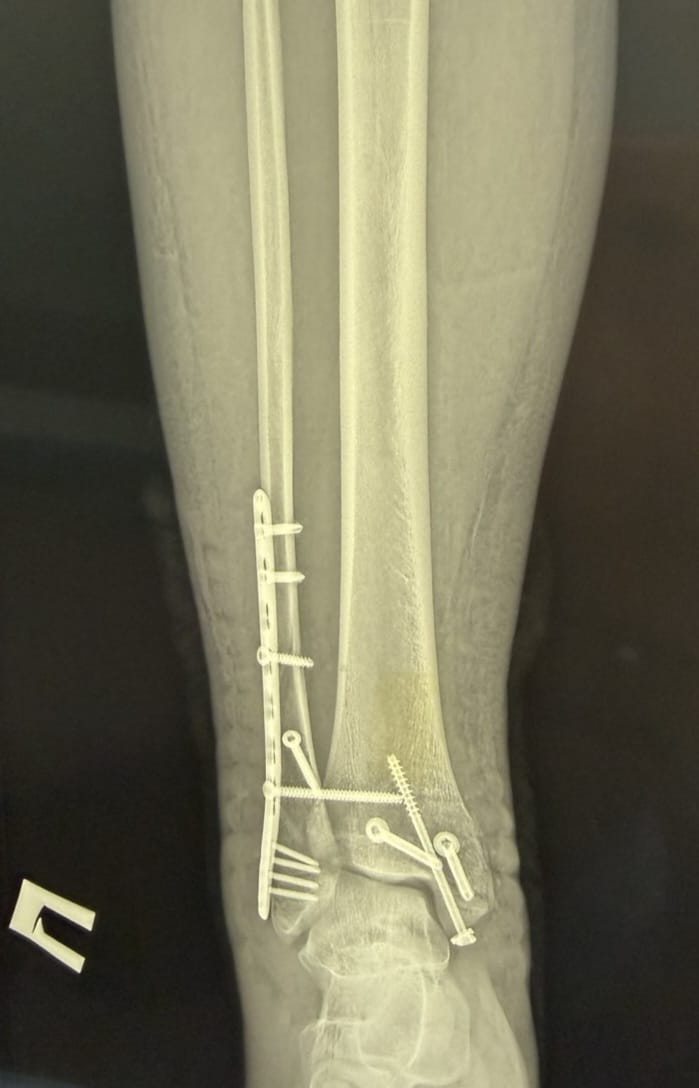

- закритий перелом правої малогомілкової кістки у нижній третині зі зміщенням;

- закритий перелом медіальної кісточки правої великогомілкової кістки зі зміщенням;

- закритий перелом заднього краю дистального відділу правої великогомілкової кістки зі зміщенням.

- відкрите зіставлення уламків правої малогомілкової кістки та остеосинтез пластиною і гвинтами;

- репозицію переломів медіальної кісточки та заднього краю дистального відділу великогомілкової кістки з фіксацією гвинтами;

- фіксацію міжгомілкового синдесмозу гвинтом для відновлення стабільності гомілковостопного суглоба.